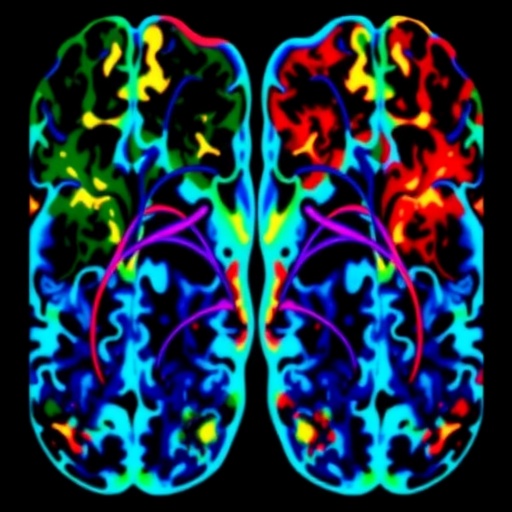

The study’s approach hinges on comparative analyses of functional brain areas — essentially, regions with coordinated activity patterns — and their spatial configurations relative to normative data. Employing advanced neuroimaging datasets and sophisticated statistical frameworks, the team meticulously quantified variations in the size, shape, and positioning of these functional areas across large cohorts of patients and controls. This methodological precision marks a departure from earlier studies, which primarily relied on global connectivity indices or less refined regional analyses prone to averaging out meaningful heterogeneity.

One of the pivotal revelations from this replication effort was the consistent demonstration of altered topography within the default mode network (DMN) and salience network — two networks heavily implicated in self-referential thought, cognitive control, and the processing of salient stimuli. The DMN, commonly associated with introspective mental activity, showed reductions not only in overall functional area but also exhibited atypical spatial displacement when compared to neurotypical counterparts. Concurrently, the salience network, which mediates attention and the detection of behaviorally relevant stimuli, displayed comparable disruptions, suggesting a systemic reconfiguration of neural circuits critical for cognitive and emotional regulation in psychosis.

Beyond these core networks, the study provided evidence of widespread network disruption, encompassing the frontoparietal control system and subcortical hubs. The frontoparietal network, fundamental for executive functioning and decision-making, revealed diminished functional territory coupled with altered regional interplay, potentially underpinning the cognitive deficits observed in non-affective psychosis. Meanwhile, aberrations in subcortical structures hint at complex pathophysiological mechanisms that might drive dopaminergic dysregulation and affective disturbances characteristic of these illnesses.

It is worth noting that the study deploys state-of-the-art neuroimaging modalities, predominantly resting-state functional magnetic resonance imaging (fMRI), which captures spontaneous brain activity patterns with exquisite temporal and spatial resolution. Coupled with robust preprocessing techniques to minimize noise and artifact influence, the dataset ensures high-fidelity data upon which the FUNCATA framework operates. These technical refinements are critical given that subtle topographical changes necessitate granular data precision to avoid confounding interpretations.